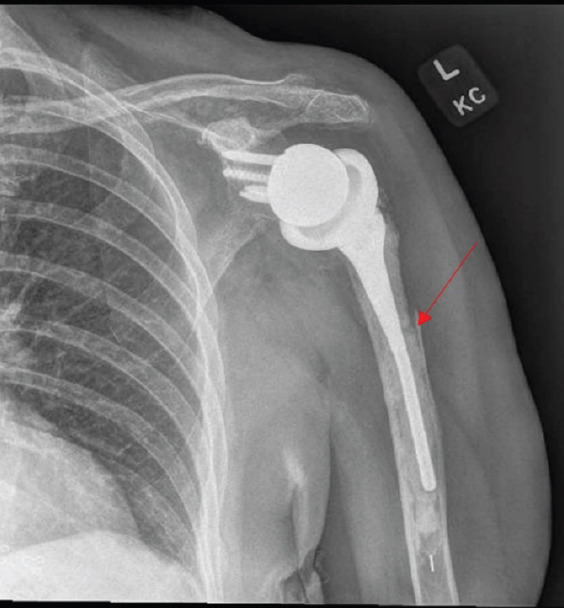

Introduction: Reverse total shoulder arthroplasty (RTSA) is increasingly performed, with a corresponding rise in associated complications such as periprosthetic fractures. Although implant failure and loosening are well documented, deformation of a humeral stem without loosening has not been previously reported.

Case report: A 77-year-old woman, 9 years after an RTSA, presented with left shoulder pain after a fall. Initial radiographs revealed a transverse periprosthetic proximal diaphyseal fracture and a deformed humeral component. She was treated nonoperatively with range-of-motion exercises and pain management. One year later, radiographs confirmed fracture healing, and the patient had no pain and had regained full motion.

Conclusion: This is the first reported case of deformation of a humeral stem in a shoulder arthroplasty. Nonoperative management was successful for fracture healing.